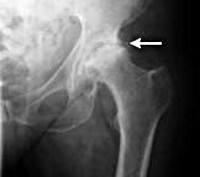

M16 Коксартроз [артроз тазобедренного сустава]

Остеоартроз - гетерогенная группа заболеваний различной этиологии со сходными биологическими, морфологическими, клиническими проявлениями и исходом, в основе которых лежит поражение всех компонентов сустава (хрящ, субхондральная кость, синовиальная оболочка, связки, капсулы, околосуставные мышцы). Характеризуется клеточным стрессом и деградацией экстрацеллюлярного матрикса всех тканей сустава, возникающих на фоне макро- и микроповреждений, при этом активируются ненормальные адаптивные восстановительные ответы, включая провоспалительные пути иммунной системы. Первоначально изменения происходят на молекулярном уровне с последующими анатомическими и физиологическими нарушениями (включая деградацию хряща, костное ремоделирование, образование остеофитов, воспаление).

Первичный и вторичный остеоартроз - развивается на фоне различных заболеваний, травм суставов. Первичный возникает, как правило, после 45 лет. Наиболее частой и характерной локализацией являются коленные суставы, межфаланговые суставы кистей, позвоночник, первый палец стопы и тазобедренные суставы. Женщины чаще мужчин страдают артрозом коленных суставов и суставов кистей.

Вторичный артроз по своим клиническим проявлениям не отличается от первичного, развивается практически в любых суставах и имеет конкретную причину заболевания.